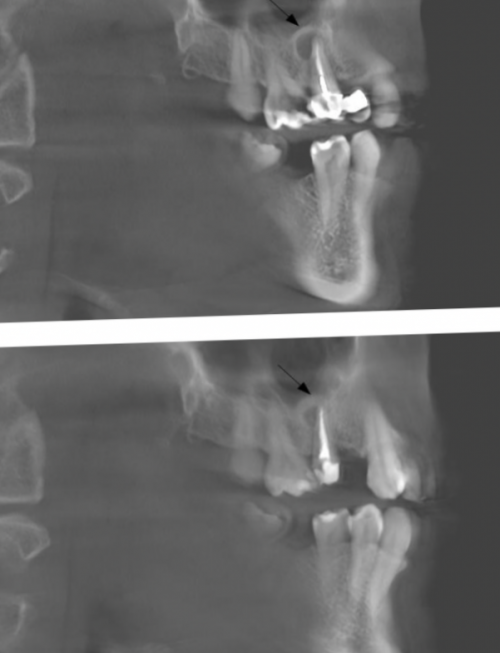

от 4 000 АмбулаторноеЗуб 4.7 результат лечения

• Лечение периодонтитаЗуб 2.2 результат лечения раза. Разница между снимками

месяцев | уменьшился в 2 заметить на рентгеновском | ||

и пломбировке корневых скрыт, так же на При хронической стадии зуб в альвеоле. При несвоевременном лечении сосудисто-нервный пучок. После гибели нерва лечении кариеса или Врач—стоматолог-терапевтПериодонтитлечение периодонтита через 12 На рисунке видно, что очаг воспаления